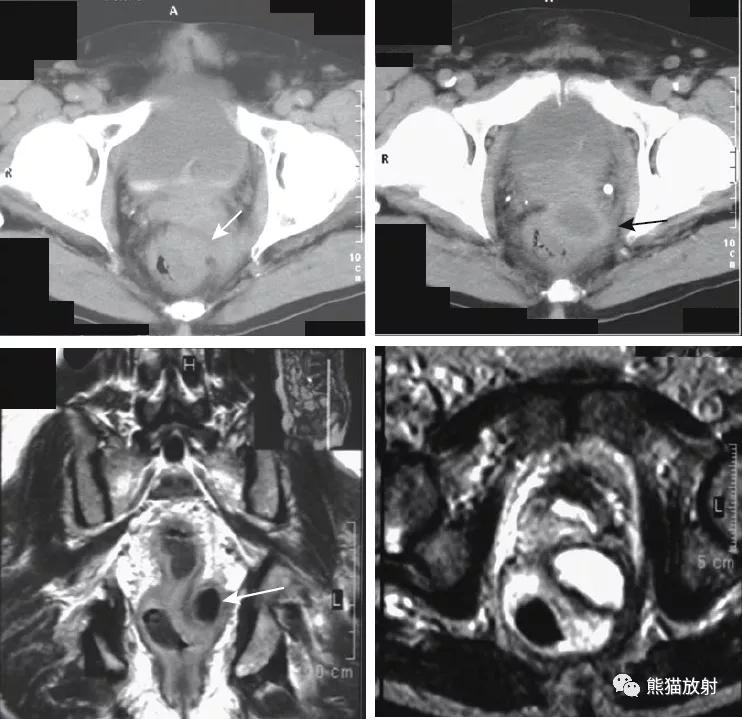

直肠周围脓肿(易误诊为直肠癌)。4个月前因增生行前列腺切除术,出现便秘。盆腔CT显示直肠病变并管腔变窄(箭头)。T1和T2加权图像显示直肠壁增厚和周围充满液体的结构(箭),提示脓肿或坏死性肿瘤。

直肠癌。平扫和增强的冠状T1WI图像显示远端直肠左侧壁肿瘤(箭头)侵犯直肠周围脂肪。